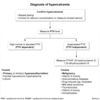

how are pregnant patients screened for hyperthyroidism? (3)

torn

TSH

(low TSH) ➜ [free T4]

(normal [free T4]) ➜ [Total T3]

use trimester-specific norms